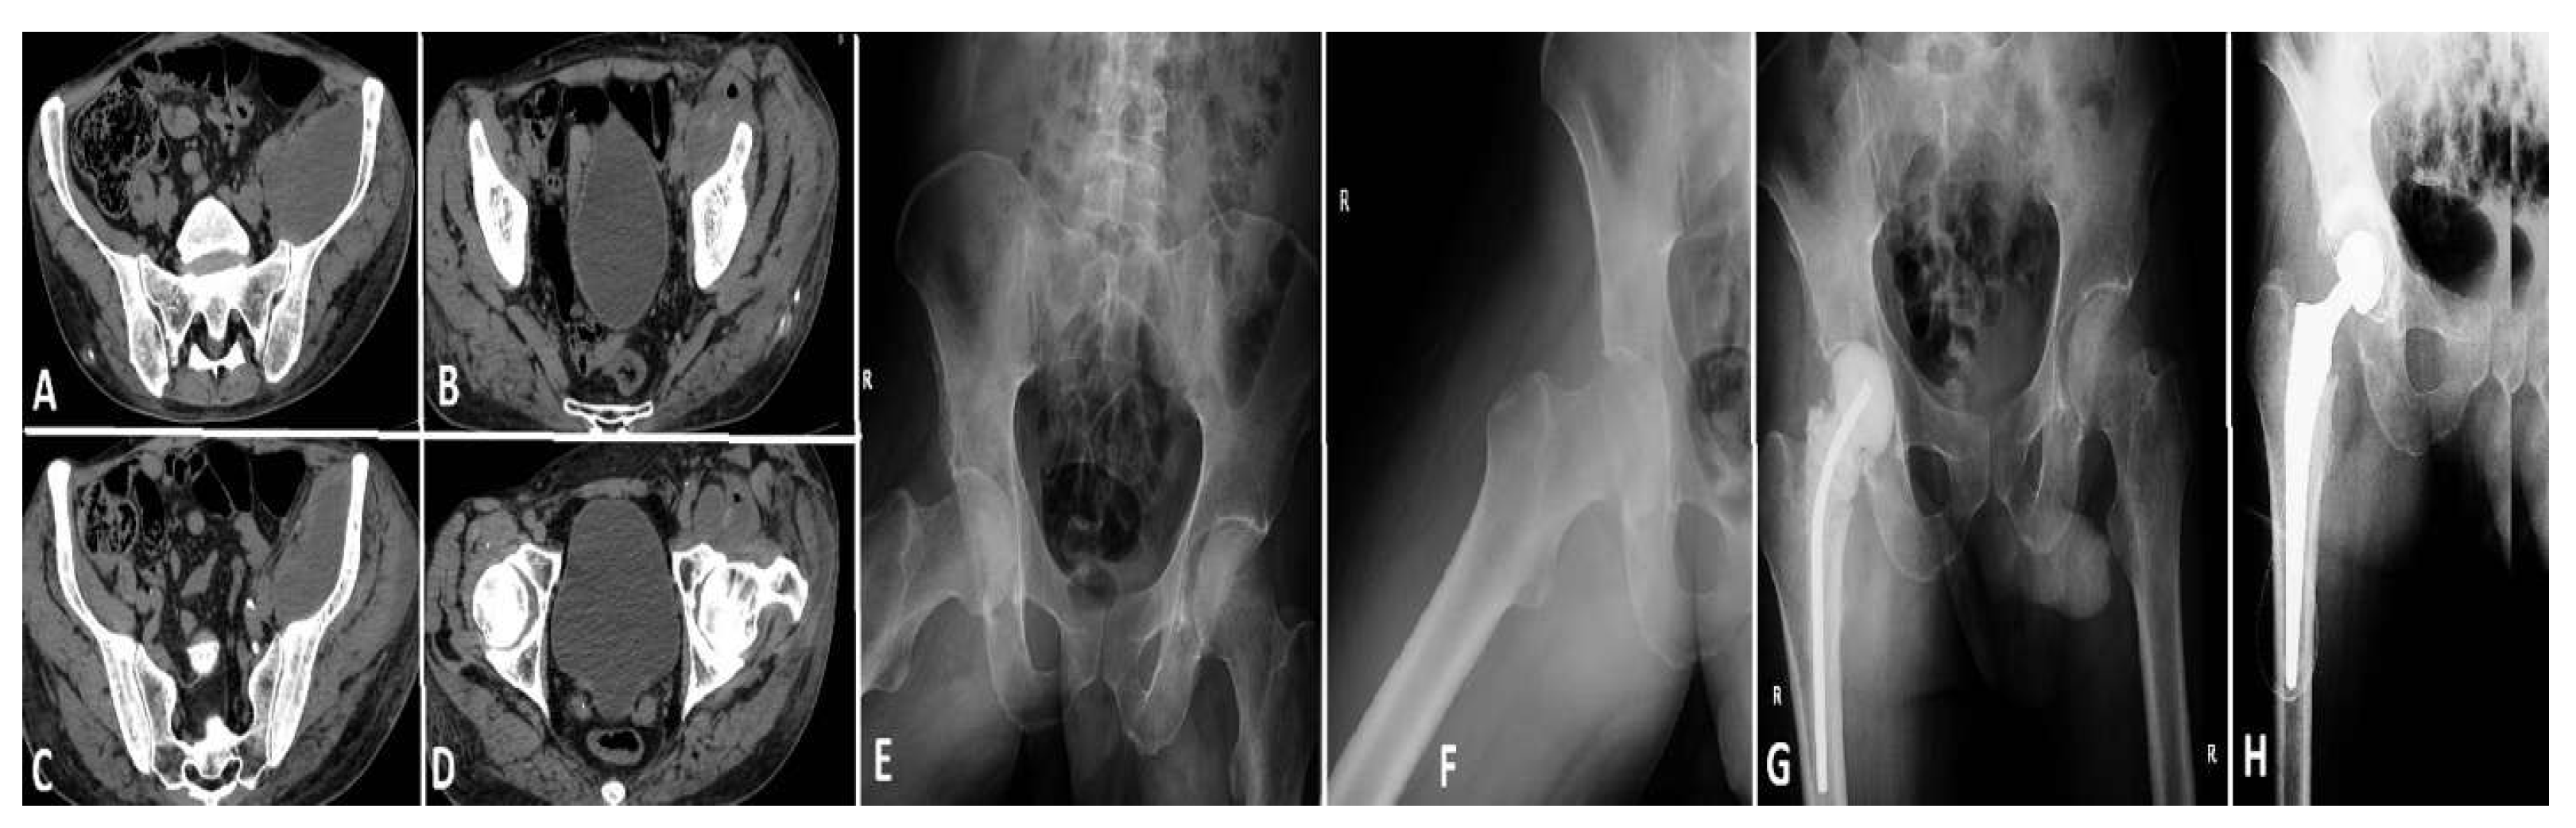

Case 2 (see Figure 7): A 54-year-old male, despite being younger than the typical age for this condition, exhibited a considerable number of comorbidities, including a history of myocardial infarction, diabetes mellitus, persistent smoking, alcohol misuse, and a cachectic appearance. The patient was a pedestrian involved in a road traffic accident three months prior, yet did not seek medical attention at the time. The patient presented at the hospital three months after the incident with severe left hip pain. Imaging and clinical evaluation indicated the presence of purulent discharge from the left hip, while laboratory tests demonstrated a notable elevation in inflammatory markers. The patient was transferred to the ICU with sepsis and underwent a hip osteotomy, followed by the insertion of an antibiotic-impregnated spacer. Following intensive antimicrobial treatment and supportive care in the ICU, the patient’s condition showed signs of improvement. However, due to the presence of chronic health issues and an elevated risk of infection recurrence, the long-term prognosis remained uncertain.

Figure 7. Depicts three images, labeled (AC), which illustrate a significant pelvic abscess that extends along the iliopsoas muscle and reaches the femoral head. This collection indicates a profound infection, with the potential to affect both the muscle and the surrounding joint components. Image (D) illustrates the abscess encircling the femoral head, thereby emphasizing the severity of the infection in this vital anatomical area. Images (E,F) illustrate the conventional anteroposterior and lateral radiographs of the hip joint, respectively. Despite the X-rays failing to provide sufficient information to elucidate the diagnosis, the patient’s ongoing and intense discomfort necessitated additional imaging via a CT scan, which ultimately disclosed the full extent of the illness. Image (G) depicts the surgical debridement of the infected joint focus, accompanied by the insertion of an antibiotic-impregnated cement spacer. The objective of this provisional implant is to manage the infection while ensuring the mechanical stability of the joint. In Image (H), the hip arthroplasty is depicted, conducted approximately six months following the initial surgical procedure, when the infection was successfully managed, thereby allowing for the placement of the definitive prosthesis.